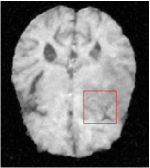

All the experiments are implemented on a Windows workstation with Intel Core i9 CPU at 3.3GHz and an Nvidia GTX-1080Ti GPU with 11GB of graphics card memory via TensorFlow Abadi et al. (2016). The parameters in the proposed network are initialized by using Xavier initialization Glorot and Bengio (2010). We trained the meta-learning network with four tasks synergistically associated with four different CS ratios: 10%, 20%, 30%, and 40%, and test the well-trained model on the testing dataset with the same masks of these four ratios. We have 300 training data for each CS ratio, which amount to total of 1200 images in the training dataset. The results for and MR reconstructions are shown in Tables 5.4 and 5.4 respectively. The associated reconstructed images are displayed in Figures 1 and 3. We also test the well-trained meta-learning model on unseen tasks with radio masks for skewed ratios: 15%, 25%, 35%, and random Cartesian masks with ratios 10%, 20%, 30% and 40%. The task-specific parameter for the unseen tasks are retrained for different masks with different sampling ratios individually with fixed task-invariant parameters . In this experiments, we only need to learn for three skewed CS ratios with radio mask and four regular CS ratios with Cartesian masks. The experimental training proceed on less data and iterations, where we performed on 100 MR images with 50 epochs. For example, for reconstructing MR images with CS ratio 15% radio mask, we fix the parameter and retrain the task-specific parameter on 100 raw data with 50 epochs, then test with renewed on our testing data set with raw measurement that sampled from radio mask with CS ratio 15%. The results associated with radio masks are shown in Table 5.4 and 5.4, Figure 2 and 4 for and images respectively. The results associated with Cartesian masks are list in Table 5.4 and reconstructed images are displayed in Figure 5.

In this section, we test the generalizability of the proposed model that tests on unseen tasks. We fix the well-trained task-invariant parameter and only train for sampling ratios 15%, 25% and 35% with radio masks and sampling ratios 10%, 20%, 30% and 40% with Cartesian masks. In this experiment, we only used 100 training data for each CS ratio and apply a total of 50 epochs. The averaged evaluation values and standard deviations are listed in Table 5.4 and 5.4 for reconstructed T1 and T2 brain images respectively that proceed with radio masks, and Table 5.4 shows the qualitative performance for reconstructed T2 brain image that applied random Cartesian sampling masks. In T1 image reconstruction results, meta-learning improved 1.6921 dB in PSNR for 15% CS ratio, 1.6608 dB for 25% CS ratio, and 0.5764 dB for 35% comparing to the conventional method, which in the tendency that the level of reconstruction quality for lower CS ratios improved more than higher CS ratios. A similar trend happens in T2 reconstruction results with different sampling masks. The qualitative comparisons are illustrated in Figure 2, 4 and 5 for T1 and T2 images tested in skewed CS ratios in radio masks, and T2 images tested in Cartesian masks with regular CS ratios respectively. In the experiments that conducted with radio masks, meta-learning is superior to conventional learning especially at CS ratio 15%, one can observe that the detailed region in red boxes keeps edges and is more close to the true image, while conventional method reconstructions are hazier and lost details in some complicated tissue. The point-wise error map also indicates that Meta-learning has the ability to suppress noises.

Training with Cartesian masks is more difficult than radio masks, especially for conventional learning where the network is not very deep since the network only applied three convolutions each with four kernels. Table 5.4 indicates that the average performance of meta-learning improved about 1.87 dB comparing to conventional methods with T2 brain images. These results further demonstrate that meta-learning has the benefit of parameter efficiency, the performance is much better than conventional learning even if we apply a shallow network with small size of training data.